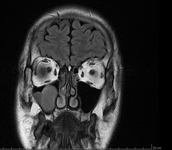

Dauunderer behauptet in seinen MRT/ OPG Bildern diverse Patienten mit DMPS Spritze geheilt zu haben. Das waren aber überwiegend Fälle aus den 90er. Dauunderer hat erst etwas später DMSA für sich entdeckt und hat umfassende Experimente durchgeführt mit eindrucksvollen Heilungen.Amalgam: weicher breiter Striemen am Boden der Kieferhöhle